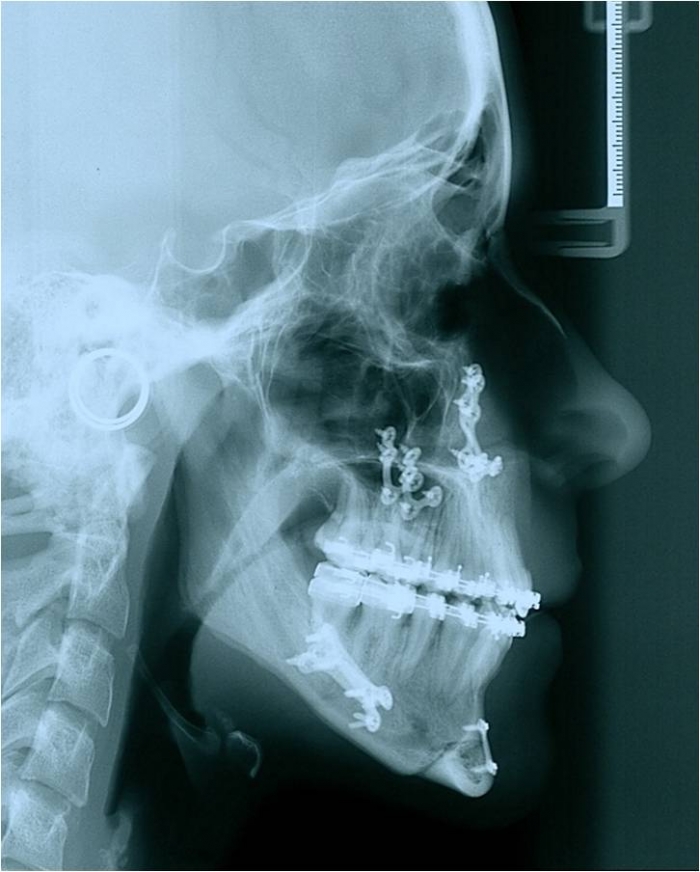

Telerradiografia de perfil após a cirurgia - Clínica Cliniface

Telerradiografia de perfil após a cirurgia